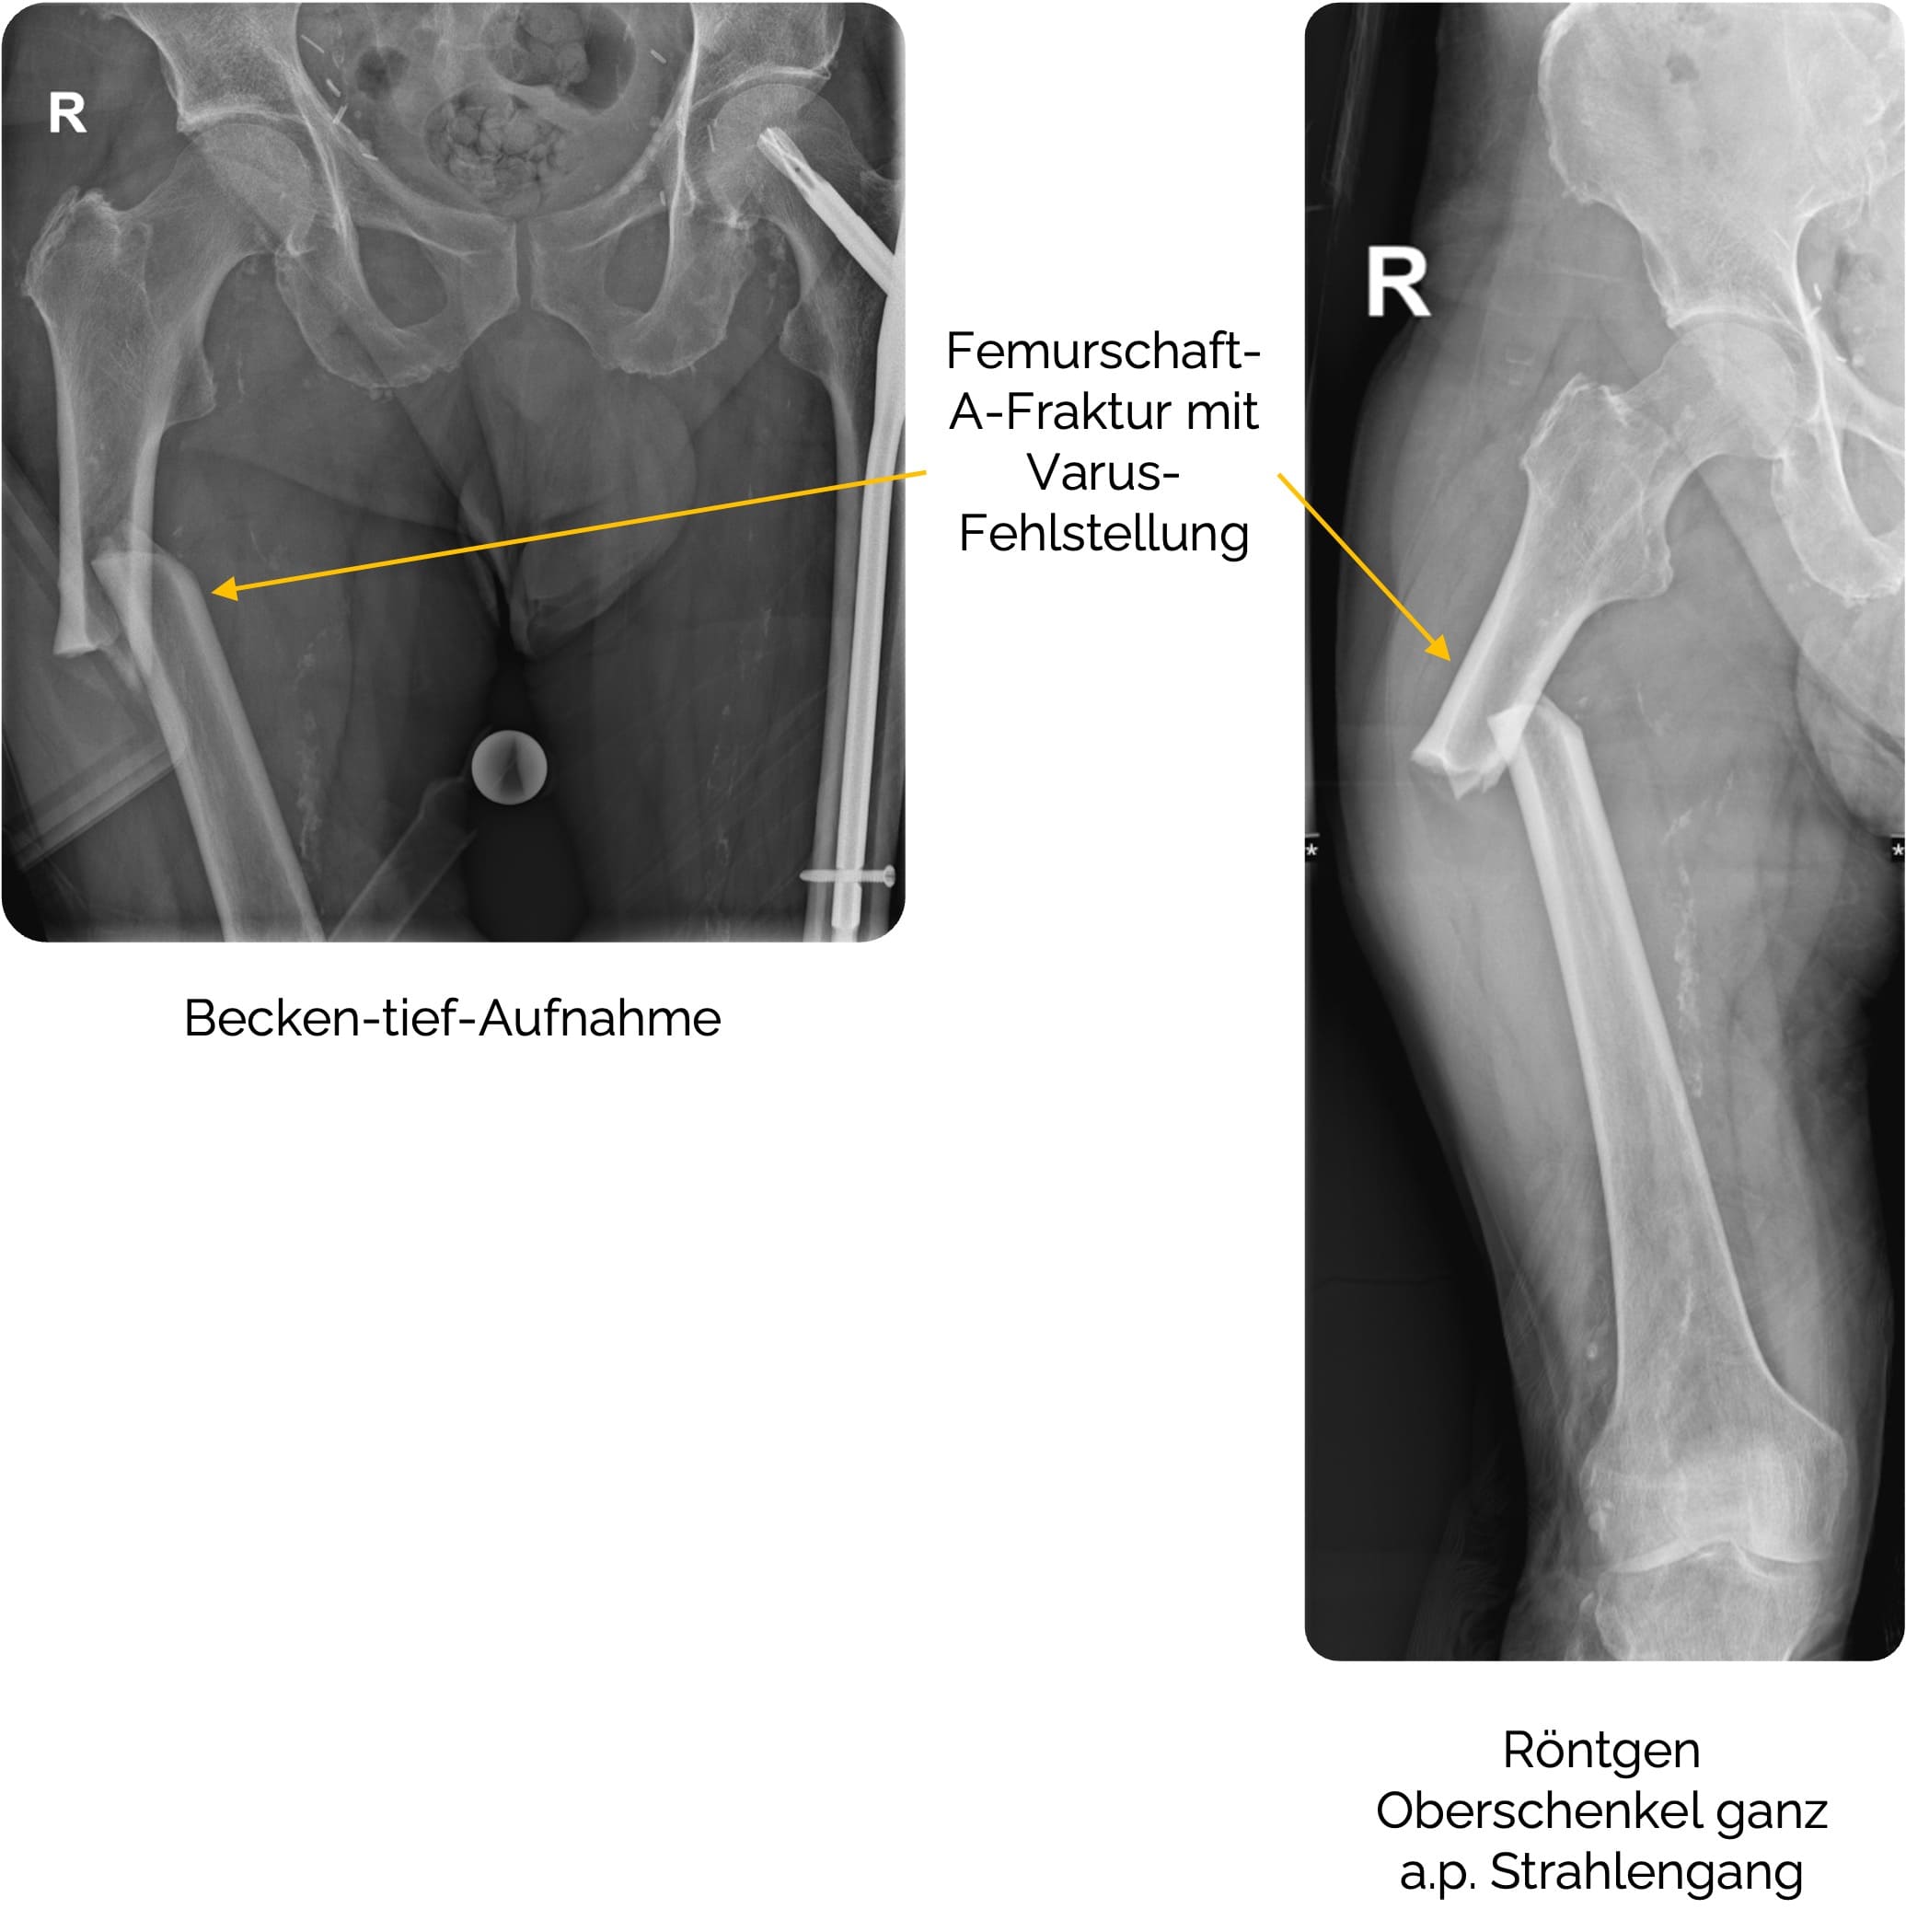

Femurschaftfrakturen

Bei Femurschaftfrakturen (AO 32) handelt sich um eine eher selten vorkommende Frakturform des Oberschenkels, die meist im Rahmen von Hochrasanztraumata, Sturz aus großer Höhe oder als

Klassifiziert werden die Femurschaftfrakturen nach der AO-Klassifikation

Zur radiologischen Diagnostik wird der Oberschenkel in 2 Ebenen (a.p. und seitlich), sowie die angrenzenden Gelenke Knie und Hüfte abgebildet (z.B. Oberschenkel mit Knie in 2 Ebenen + Beckenübersicht a.p. + Hüfte axial). Bei einem (Polytrauma-) CT mit Darstellung des geforderten Bereichs muss meist keine zusätzliche Röntgendiagnostik erfolgen.

Therapie der Femurschaftfraktur ist in der Regel

- Geschlossene Reposition mit Marknagelosteosynthese (Goldstandard) und Verriegelungsbolzen zur Rotationsstabilität. Statisch oder dynamisch mit oder ohne Markraumbohrung, teilweise additive Cerclage-Osteosynthese.